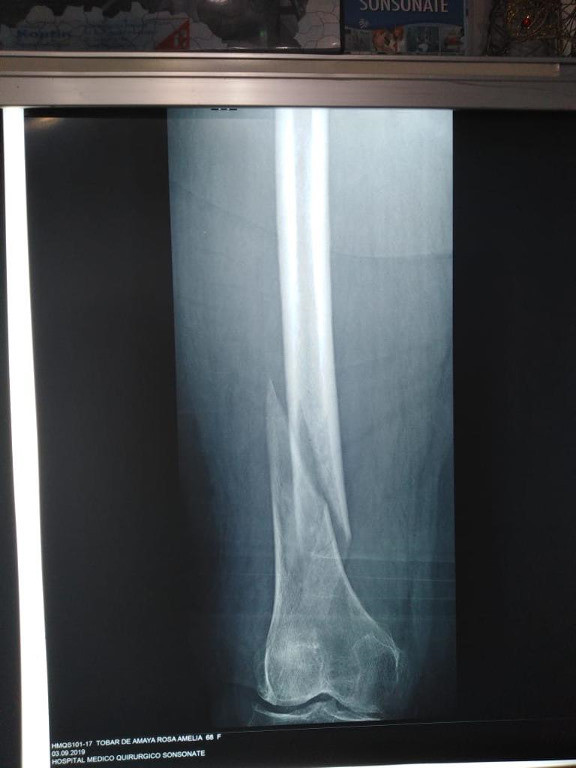

Imágenes de ortopedia y traumatología

Envíado por Dr. José Israel Flores Hernández